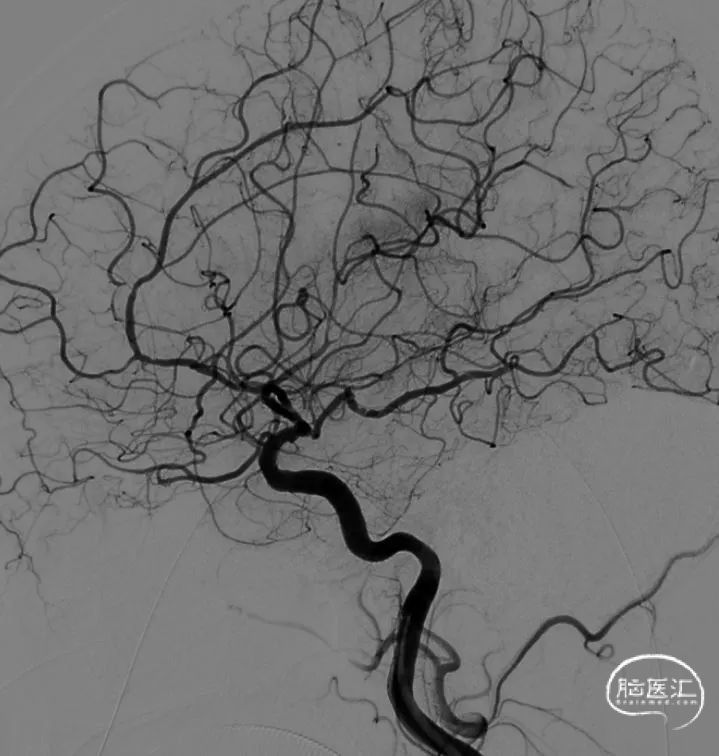

术后造影

患者出院时查体:神志嗜睡,可简单言语,左上肢肌力2级,下肢2级。NIHSS评分12分。

3月后临床复查,患者神志清,对答切题,左侧肢体肌力3级,NIHSS评分8分。